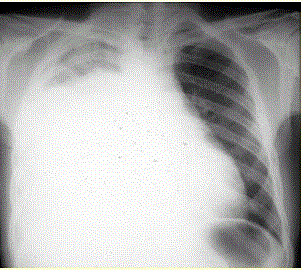

问题  患者男,34岁。进行性胸闷、气促1个月余,伴有干咳、右胸隐痛以及消瘦,无咯血、发热、盗汗、潮热等。 该患者目前的处理措施正确的是

选项 A、静脉给予广谱抗生素 B、紧急外科手术 C、给予紧急配血和输血 D、使用糖皮质激素 E、高流量吸氧 F、静脉给予肾上腺素 G、加快胸腔积液的引流 H、静脉溶栓 I、静脉给予利尿药 J、必要时机械通气

答案 DEIJ

解析 DEIJ